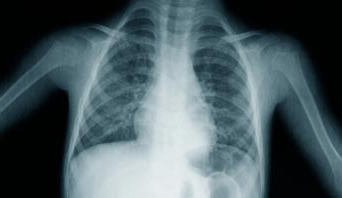

X-rays are the most frequently used ionising radiation in diagnostics. They were used in medicine within a year of their accidental discovery in 1896 by Konrad Roentgen. They are employed as an examination tool but also in therapy. X-ray pictures allow doctors to see what’s happening inside the human body without having to open it up. In typical X-ray examinations the radiation dose is too low to pose any risk, however we should be more cautious when pregnant women are concerned because the potential risk to the fetus is still being debated.

For medical procedures, when the radiation is used for diagnostic purposes (like X-ray images) the dose is limited to a safe level which still allows good imaging of our organs. However, in radiotherapy, the only aim of the physician is to fight the cancer and the dose used may be very high, although targeted on the tumor, so it does not present serious danger to the healthy parts of our organism. Complications appearing after such treatment are not rare but are mostly curable.

Chest X-ray 0.02/film 1